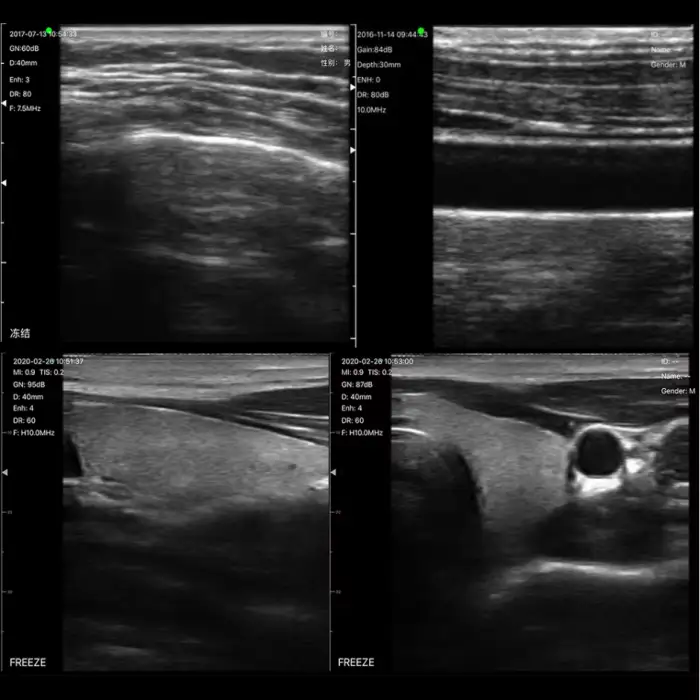

Clinic Use B/W 128 Elements Linear Probe Wireless Ultrasound Scanner Machine Available Skin Detector

1. What is the primary use of the Clinic Use B/W 128 Elements Linear Probe Wireless Ultrasound Scanner?

The primary use of this ultrasound scanner is for efficient and accurate diagnostic imaging in hospitals and clinics, particularly for routine check-ups and specialized imaging.

2. Is the ultrasound scanner wireless?

Yes, the Clinic Use B/W Ultrasound Scanner features a wireless design, allowing for easy mobility and convenience during use.

4. What frequency does the probe operate at?

The probe operates at frequencies of 10/14 MHz, providing high-resolution imaging capabilities.

5. What type of display does the scanner have?

The scanner features a black and white (B/W) display for clear imaging results.

7. Can this scanner be used for skin detection?

Yes, this ultrasound scanner is designed to detect and examine skin conditions, making it suitable for dermatological applications.

10. What are the key features of this ultrasound scanner?

Key features include high-resolution imaging with 128 elements, wireless design, multi-language support, and compact size.

11. What applications is this ultrasound scanner suitable for?

It is suitable for routine check-ups, diagnostic imaging in outpatient clinics, emergency medical services, and specialized imaging across various medical fields.

15. How does the scanner ensure high-quality imaging?

The scanner utilizes advanced technology with 128 elements and operates at high frequencies, which contribute to producing high-quality images.